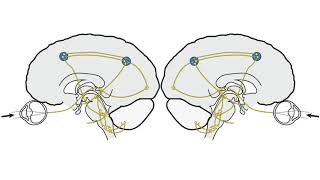

RS Supranuclear Ocular Motor Pathways Part 2 - Vertical Saccades

RS Supranuclear Ocular Motor Pathways Part 2 - Vertical Saccades RS Supranuclear Ocular Motor Pathways Part 1 - Horizontal Saccades

RS Supranuclear Ocular Motor Pathways Part 1 - Horizontal Saccades RS Supranuclear Ocular Motor Pathways Part 3 - Pursuit

RS Supranuclear Ocular Motor Pathways Part 2 - Vertical Saccades

RS Supranuclear Ocular Motor Pathways Part 2 - Vertical Saccades RS Supranuclear Ocular Motor Pathways Part 1 - Horizontal Saccades

RS Supranuclear Ocular Motor Pathways Part 1 - Horizontal Saccades RS Supranuclear Ocular Motor Pathways Part 3 - Pursuit